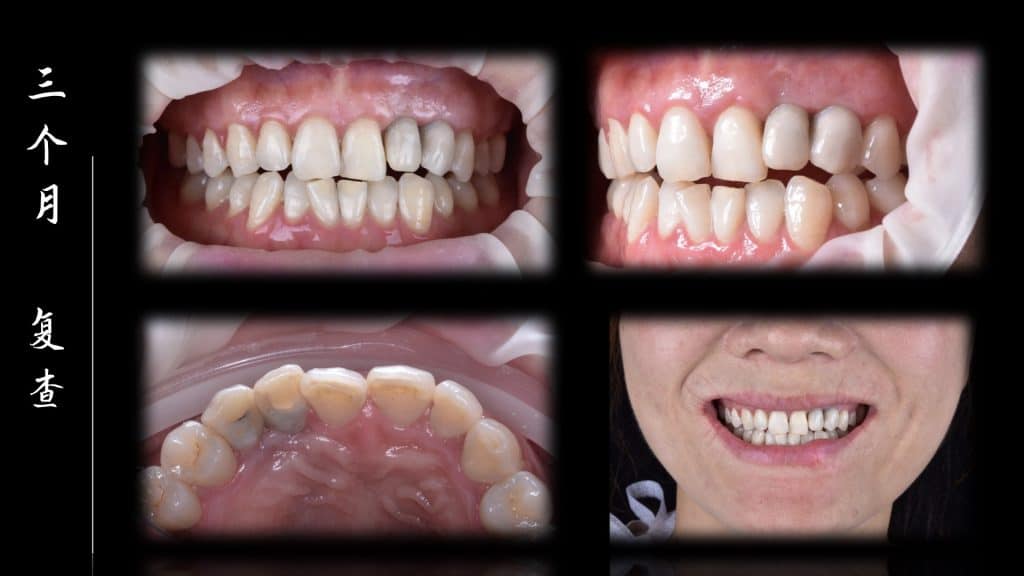

Complaint: 3 months of trauma to the upper left anterior tooth

Present medical history: 3 months ago, the left upper anterior tooth was traumatized and lost, and it was not repaired in our hospital

Before the start of this case, we did a fine digital design, including the design and production of temporary teeth, then CBCT matched the oral scan, designed the implant position, designed the incision method of our gums, and then implanted, and immediately repaired after completion, made a personalized gingival counter, and made a permanent restoration after 3 months.